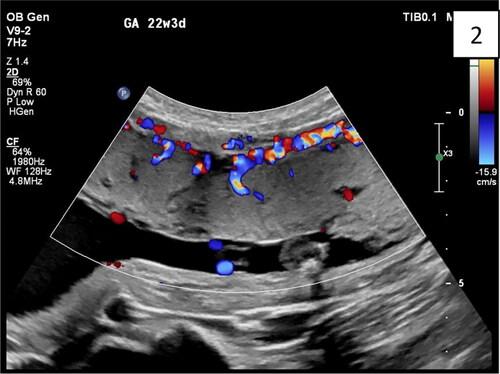

● Doppler markers (bridging vessels, hypervascularity)